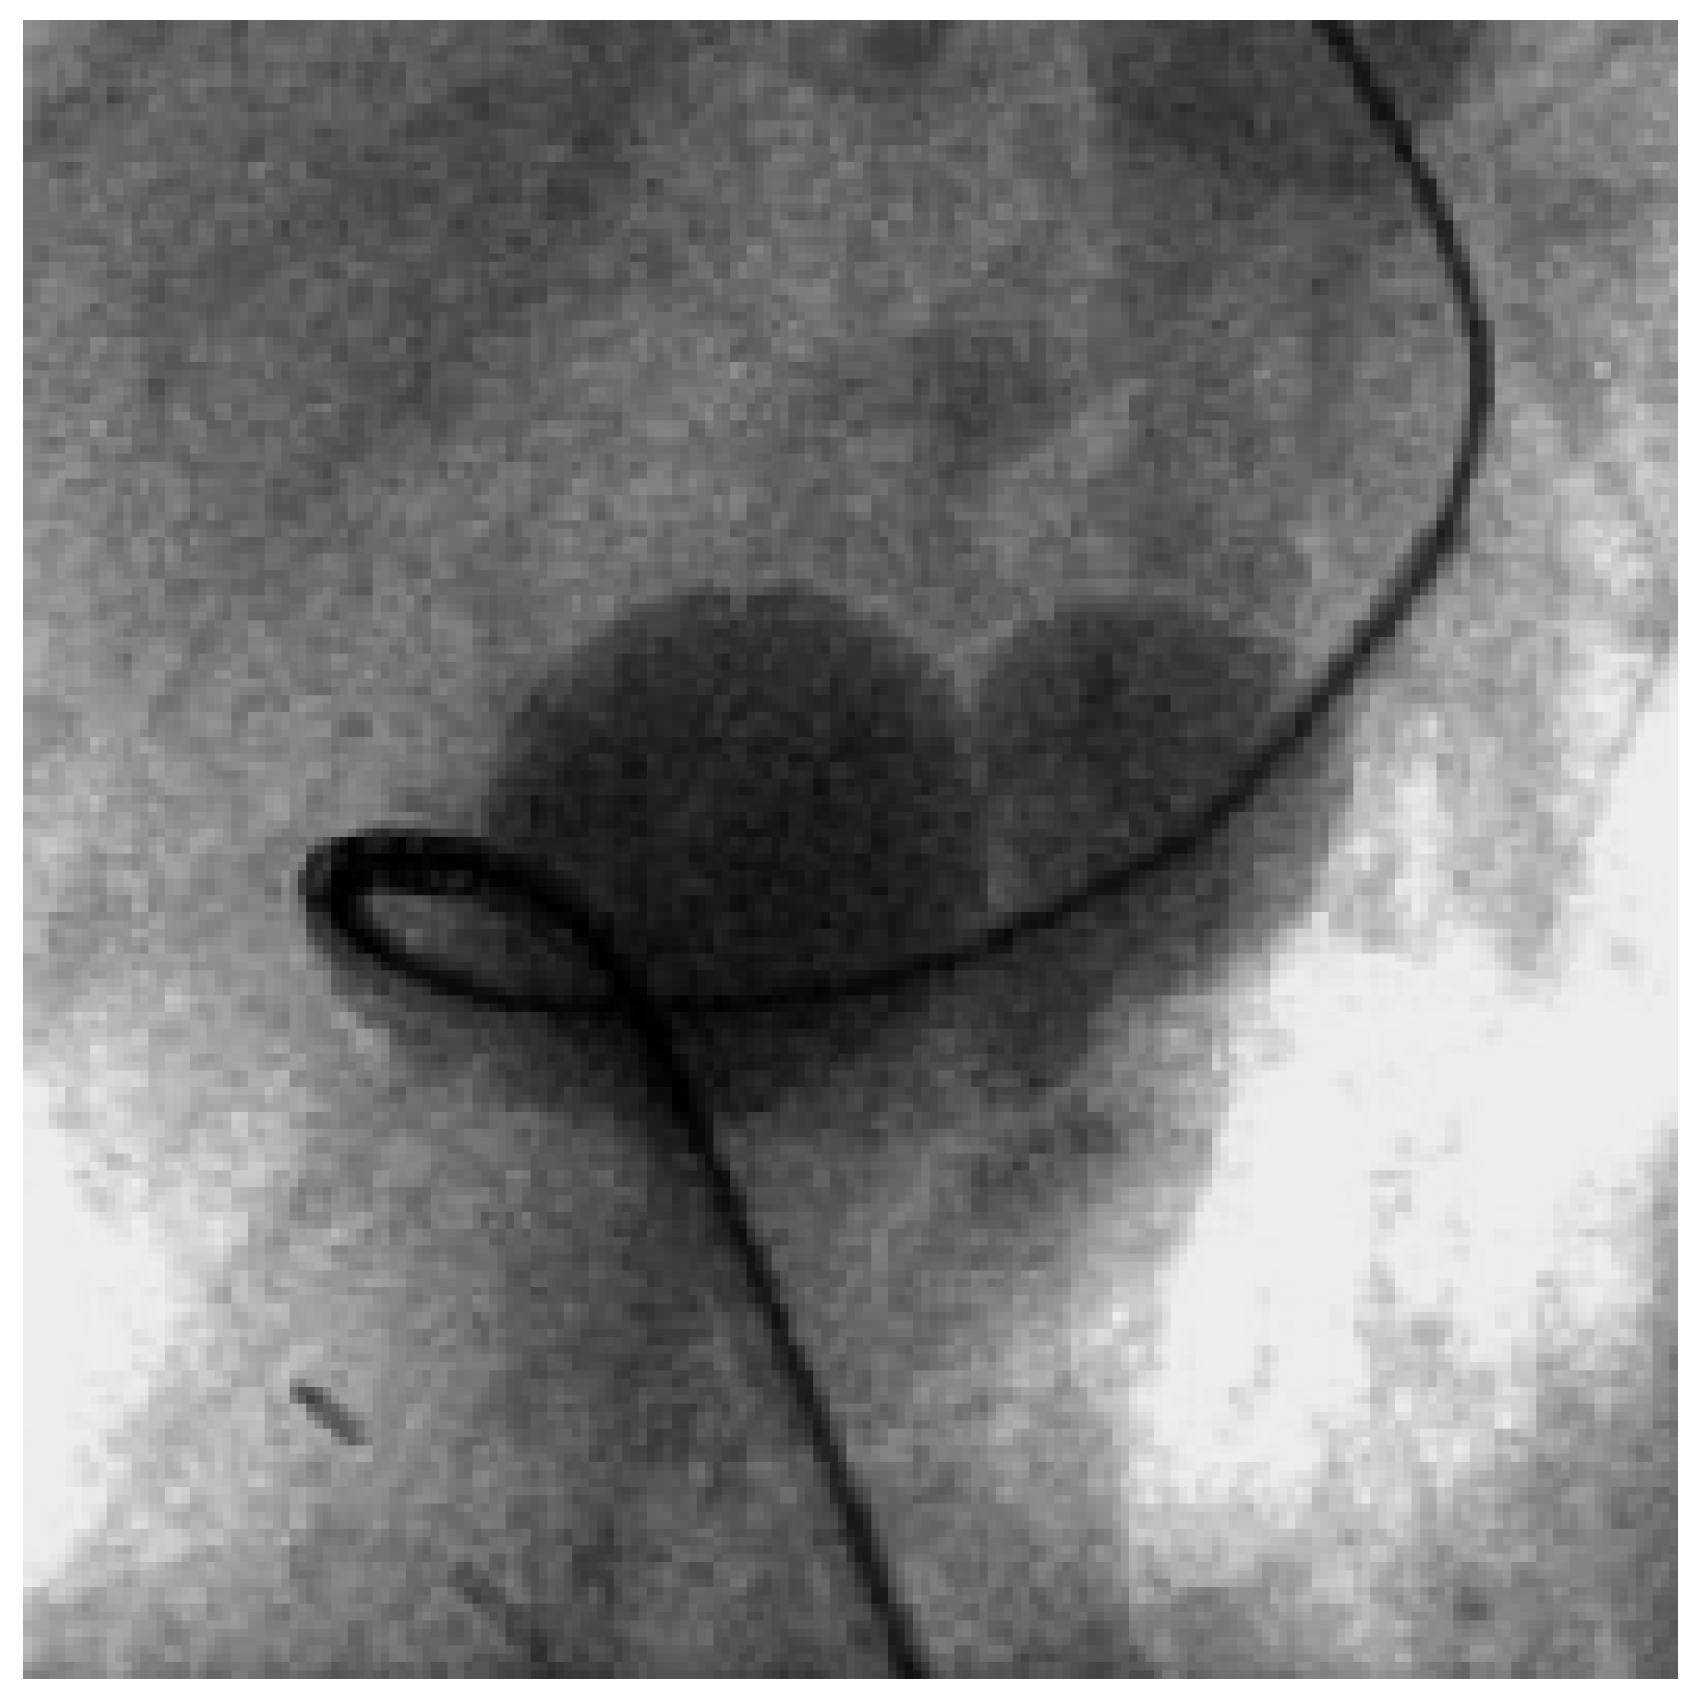

Traumatic Tamponade and Ventricular Septal Defect

Case report